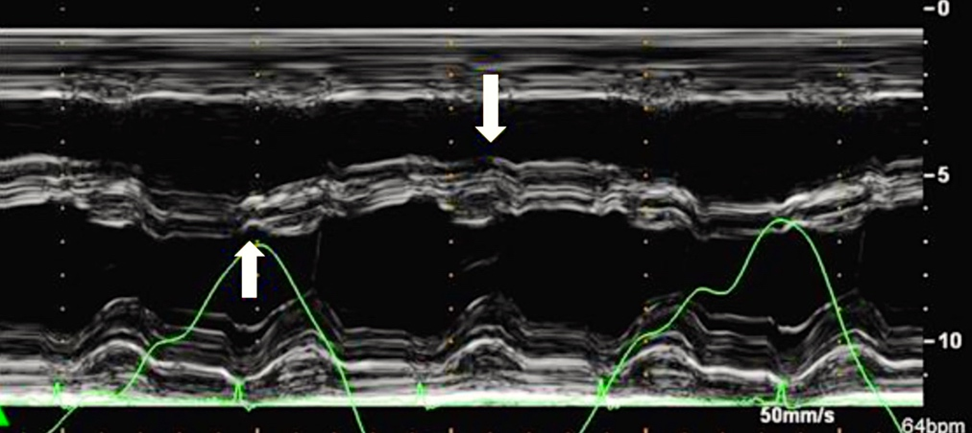

При констриктивном перикардите имеется значительная зависимость профиля кровотока через митральный и трикуспидальный клапаны от фаз дыхания:

- по данным импульсно-волновой допплерографии, в начале вдоха максимальная скорость трансмитрального пика E уменьшается на ≥25%;

- в начале выдоха максимальная скорость транстрикуспидального пика E уменьшается на ≥40% (Приложение А3, рис. А3-1) [116].

Характерно динамическое изменение атриовентрикулярного кровотока в зависимости от фазы дыхания (Приложение А3, рис. А3-6), что отличает констриктивный перикардит от рестриктивной кардиомиопатии. На вдохе пиковая скорость крови уменьшается, а время изометрического расслабления желудочков увеличивается. На выдохе — атриовентрикулярный кровоток возвращается к нормальным значениям. Как правило, прирост пиковой скорости составляет ≥25% на вдохе по сравнению с выдохом [129]. Этот признак обладает 85% чувствительности и 90% специфичности [118].

Обычно при тампонаде сердца в разные фазы дыхания наблюдаются значительные изменения трансмитрального и транстрикуспидального потоков. Во время первого сокращения сердца после вдоха максимальная скорость трансмитрального пика E уменьшается более чем на 30%, в то время как во время первого сердечного сокращения после выдоха максимальная скорость транстрикуспидального пика E уменьшается более, чем на 60% [142, 143].